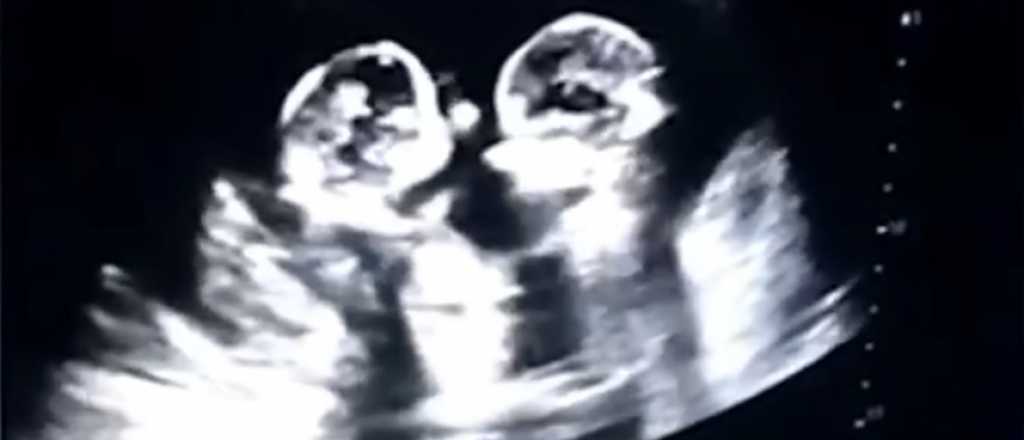

Video: gemelas a los "golpes" en la panza de su mamá

Tao, un hombre chino que fue padre de gemelas, difundió una filmación de una ecografía donde se ve a las dos niñas en la panza de su mamá "peleando a los golpes".

Las bebés nacieron de forma saludable en los últimos días, según informaron. Habría preocupación porque pertenecían a un grupo pequeño de gemelos monoamnióticos monocoriales, que representan uno de los embarazos más riesgosos y extraños y sólo 50% sobrevive después de las 26 semanas.

Entre las principales complicaciones que tiene este tipo de embarazo se encuentra que los cordones umbilicales se enredarán y anudarán. Esto produce que en uno o en los dos bebés el flujo sanguíneo sea deficiente.